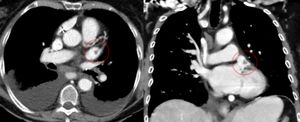

좌심방의 윗부분에는 근육질의 귀 모양 주머니, 즉 '''좌심방이'''('''LAA''', auricula atrii sinistra|아우리쿨라 아트리 시니스트라la)가 있는데, 이는 튜브 모양의 소주 구조를 가지고 있다.[9] CT 스캔으로 본 좌심방이(LAA) 해부학적 구조는 닭 날개형(48%), 선인장형(30%), 풍선형(19%), 콜리플라워형(3%)의 4가지 그룹 중 하나로 특징지어진다.[10][11] 콜리플라워형은 색전증과 가장 자주 연관되는 형태이다.[11] 좌심방이는 "좌심실 수축기 및 좌심방 압력이 높을 때 감압 챔버 역할을 한다"고 여겨진다.[12] 또한 나트륨 이뇨 펩타이드인 심방 나트륨 이뇨 펩타이드(ANP)와 뇌 나트륨 이뇨 펩타이드(BNP)를 관상 정맥동으로 분비하여 혈관 내 용적을 조절하며, 여기서 혈액 순환으로 들어간다.[13]

좌심방이는 표준 후전방 X-레이에서 좌측 폐문 하단이 오목하게 나타나는 것을 통해 확인할 수 있다.[14] 또한 경식도 심장 초음파 검사를 사용하여 명확하게 볼 수 있다.[15] 좌심방이는 승모판 수술에 접근하는 통로로 사용될 수 있다.[16]

좌심방이의 몸체는 좌심방 앞쪽에 위치하며 좌측 폐정맥과 평행하다. 좌측 폐동맥은 후상방으로 지나가며, 가로동에 의해 심방이와 분리된다.[17] 심방 세동에서[13] 좌심방이는 수축하는 대신 세동하여 혈액 정체를 유발하고, 이는 혈전의 형성을 촉진한다.[9] 그로 인한 뇌졸중 위험 때문에 외과 의사는 개심 수술 중에 좌심방이 폐쇄 시술을 사용하여 좌심방이를 폐쇄할 수 있다.[18]